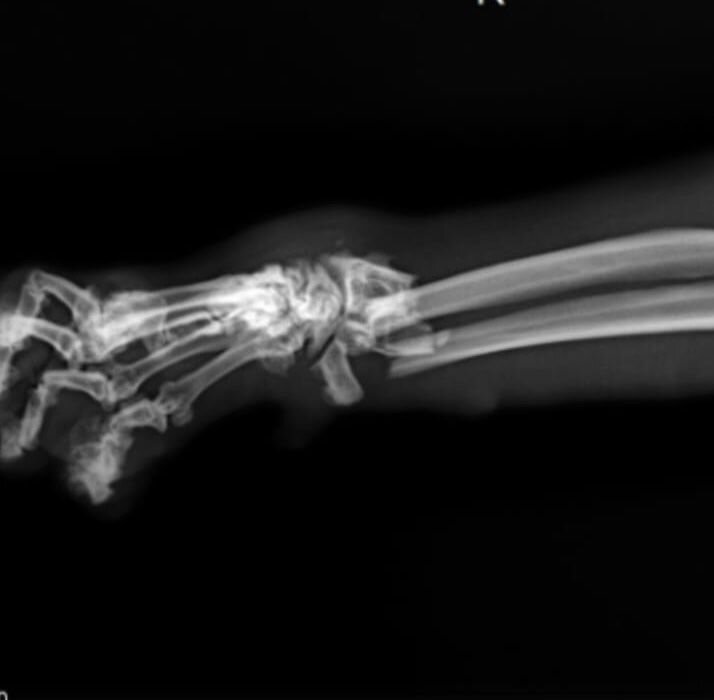

Коту лет 10. Заколтунен, пришлось побрить спину и хвост. Ужасающая остеохондродисплазия - частое заболевание скоттишей неправильного разведения - на задних лапах наросты с грецкий орех, окостенелый позвоночник и хвост, всё это очень болит.

Вкупе с двумя сломанными костями передней лапы не дает возможности бедному коту встать, он лежит, испражняется под себя. Первые дни на стрессе не ел, кормили принудительно. Как вообще огромный 7- киллограммовый кот выжил при падении с 5-го этажа - загадка. Экспресс-обследование в клинике показало, что разрывов внутренних органов и внутренних кровотечений нет, слава Богу.

30-го апреля назначена операция по остеосинтезу лапы, операционная бригада в составе: хирург - Савельев С.С., анестезиолог Ивашко Е.С., анестезист Филимонова Т.В., клиника С-Вет. Предварительная стоимость операции + предоперационное обследование 40000 руб.